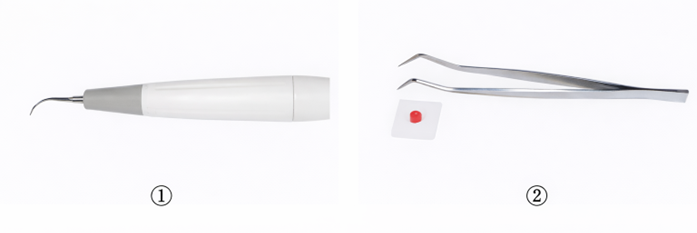

75歳の男性。慢性歯周炎に対する歯周基本治療終了後、3か月間隔で歯周病のメインテナンスと初期の根面う蝕の管理としてフッ化物歯面塗布を行っている。来院時、歯周ポケットの検査を行った後に用いる器材の写真を別に示す。 3番目に用いるのはどれか。1つ選べ。

a. ①

b. ②

c. ③

d. ④

解答を見る

d